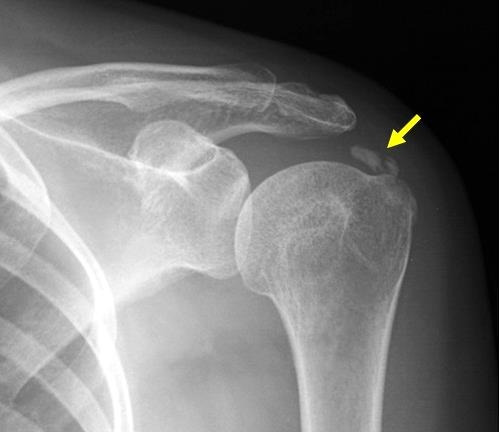

오히려, 칼슘보충제 복용으로 높아진 칼슘 수치는 심혈관을 석회화시켜 심각한 문제를 일으킬 뿐만 아니라, 팔이나 다리 혹은 어깨의 인대나 힘줄에 석회를 침착시켜 석회성 건염(calcific tendinitis)을 유발하기도 한다 [30].

건염. (1).jpg 46세 여성 좌측 어깨에 발생한 석회성 건염